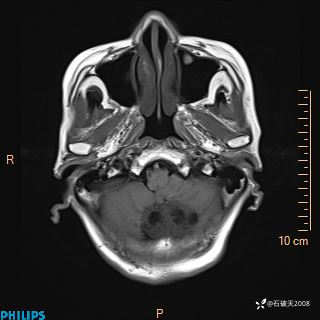

女 86岁 主 诉:乏力1月

现病史:患者1月前活动出现双下肢乏力,无头晕、头痛、恶心、呕吐、肢体活动不利,休息后缓解,间断断发作,症状进行性加重,在家口服药物治疗(具体不详),效差,为进一步诊治,来我院,门诊按“乏力”收住我科,患者自发病以来,神志清,精神稍差,饮食睡眠欠佳,大小便正常,体重未见明显改变。

T1